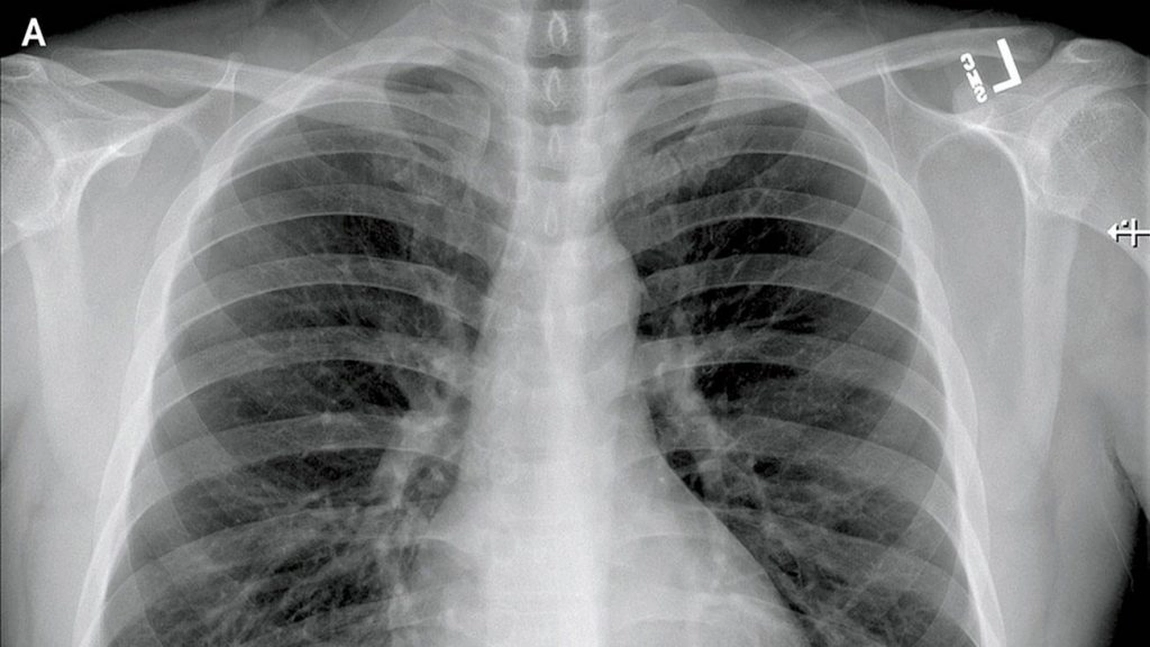

Autopsiile au relevat că coronavirusul nou atacă prima dată plămânii pacienților, a declarat Wang Guiqiang, șeful Departamentului de Boli Infecțioase din Spitalul Universitar Peking, în cadrul unei conferințe de presă la Beijing.

Autopsiile au arătat o infiltrare mare de citokine inflamatorii, cheaguri de sânge, țesut necrotic și sânge în plămâni, a spus el.

O alta constatare importanta este ca pacientii au, de asemenea, o cantitate mare de sputa care le blocheaza bronhiile, oprindu-i astfel sa obtina suficient oxigen, a spus el.